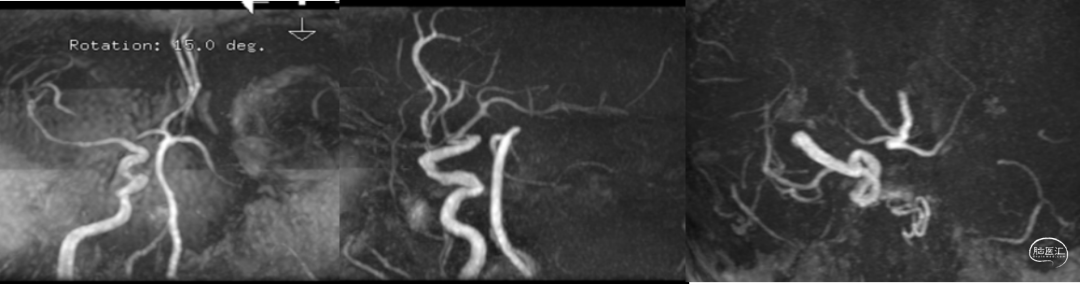

头MRA评估提示:左侧颈内动脉及大脑中动脉闭塞,见下图2。

图2.头颅MRA检查